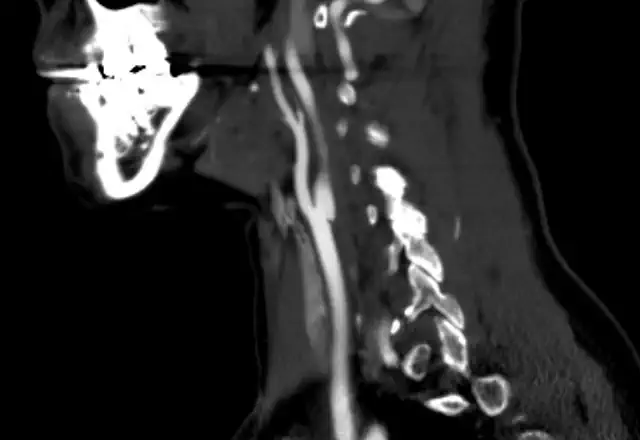

Decisions of whether to treat depend on several factors. First, whether the iliac aneurysm is isolated or not. If the iliac aneurysm accompanies an aortic aneurysm a joint decision may be a way to go. This is particularly true if the aortic aneurysm is treated with a stent-graft. Then the limbs of the graft are deployed in the iliac artery and by that the aneurysm is excluded.

Isolated aneurysms can be followed, treated with endovascular techniques or operated upon. Surgical repair is considered major vascular surgery and is risky. The literature about aneurysm size and rupture rate is disappointing, especially regarding internal iliac artery aneurysms. Once review examining all case reports to 2014 noted that aneurysms in the internal iliac artery that were asymptomatic measured 5.1 cm and those that did rupture were larger (6-7 cm).

Some series reported mortality over 10% with surgical treatment. This supports an endovascular-first approach. Endovascular treatment of iliac aneurysms involves deploying stent-grafts and excluding the aneurysmal sac. Results are not perfect, including mortality. But, the data are not as negative as for surgery. Another very negative possible outcome is graft occlusion. A recent retrospective report of 48 patients showed a 4 year primary patency of over 87.6%.